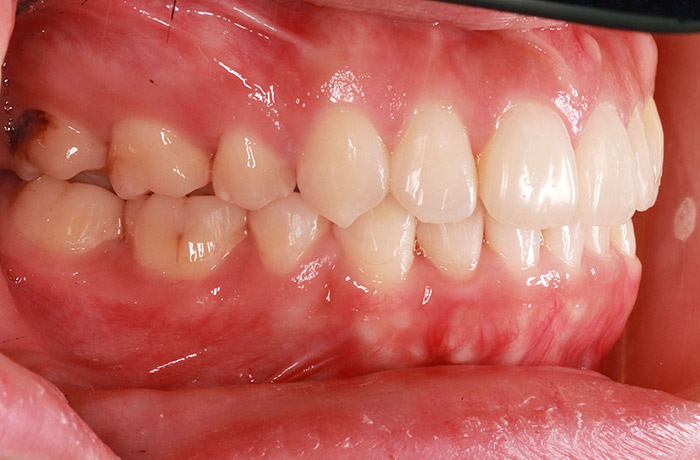

治療前

before

患者の症状 上顎前歯の凸凹

治療方法 非抜歯で、マウスピース型カスタムメイド矯正歯科装置による矯正

治療結果 歯並び、咬み合わせが良くなりました。

その他治療に関する情報 歯並びをより良くするために追加でアライナーを発注しました。

リスク/副作用 スペース不足を解消するために歯と歯の間をわずかに削合しました。